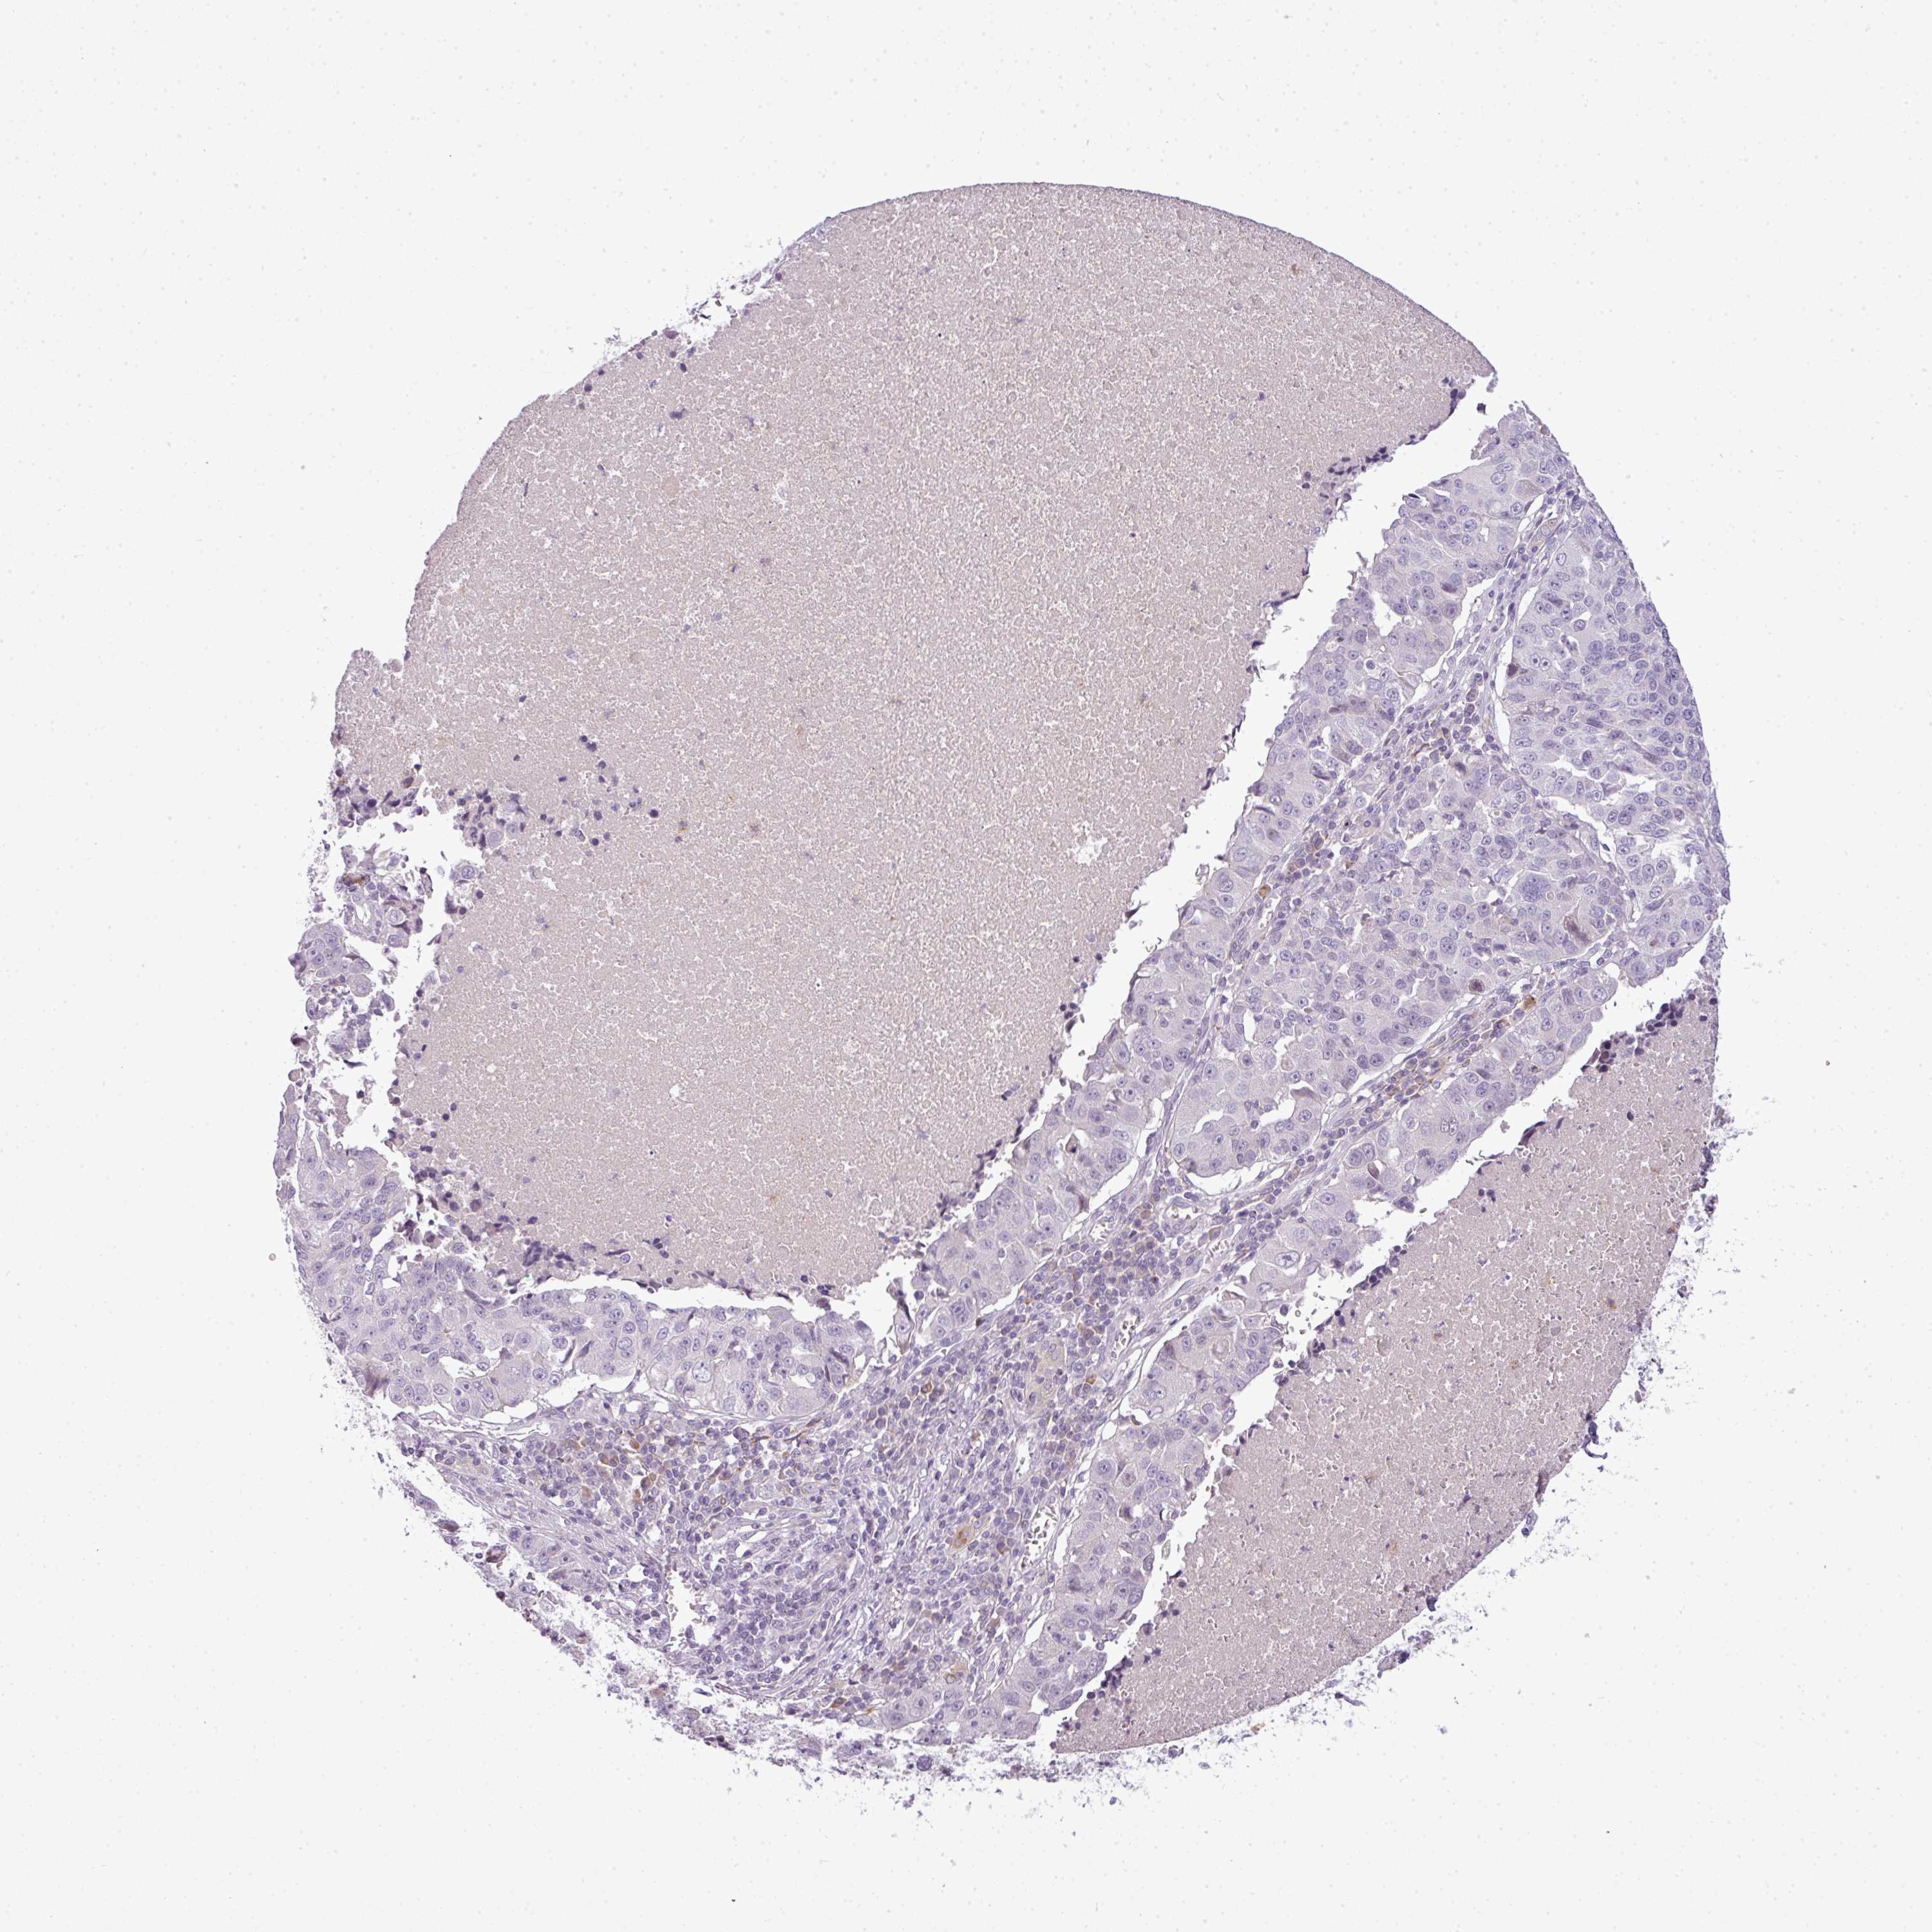

CANCER LUNG CANCER Show tissue menu

Lung cancer

Human cancer

Lung adenocarcinoma

LUNG SQUAMOUS CELL CARCINOMA (TCGA) - Interactive survival scatter ploti

C4A is not prognostic in Lung Squamous Cell Carcinoma (TCGA)